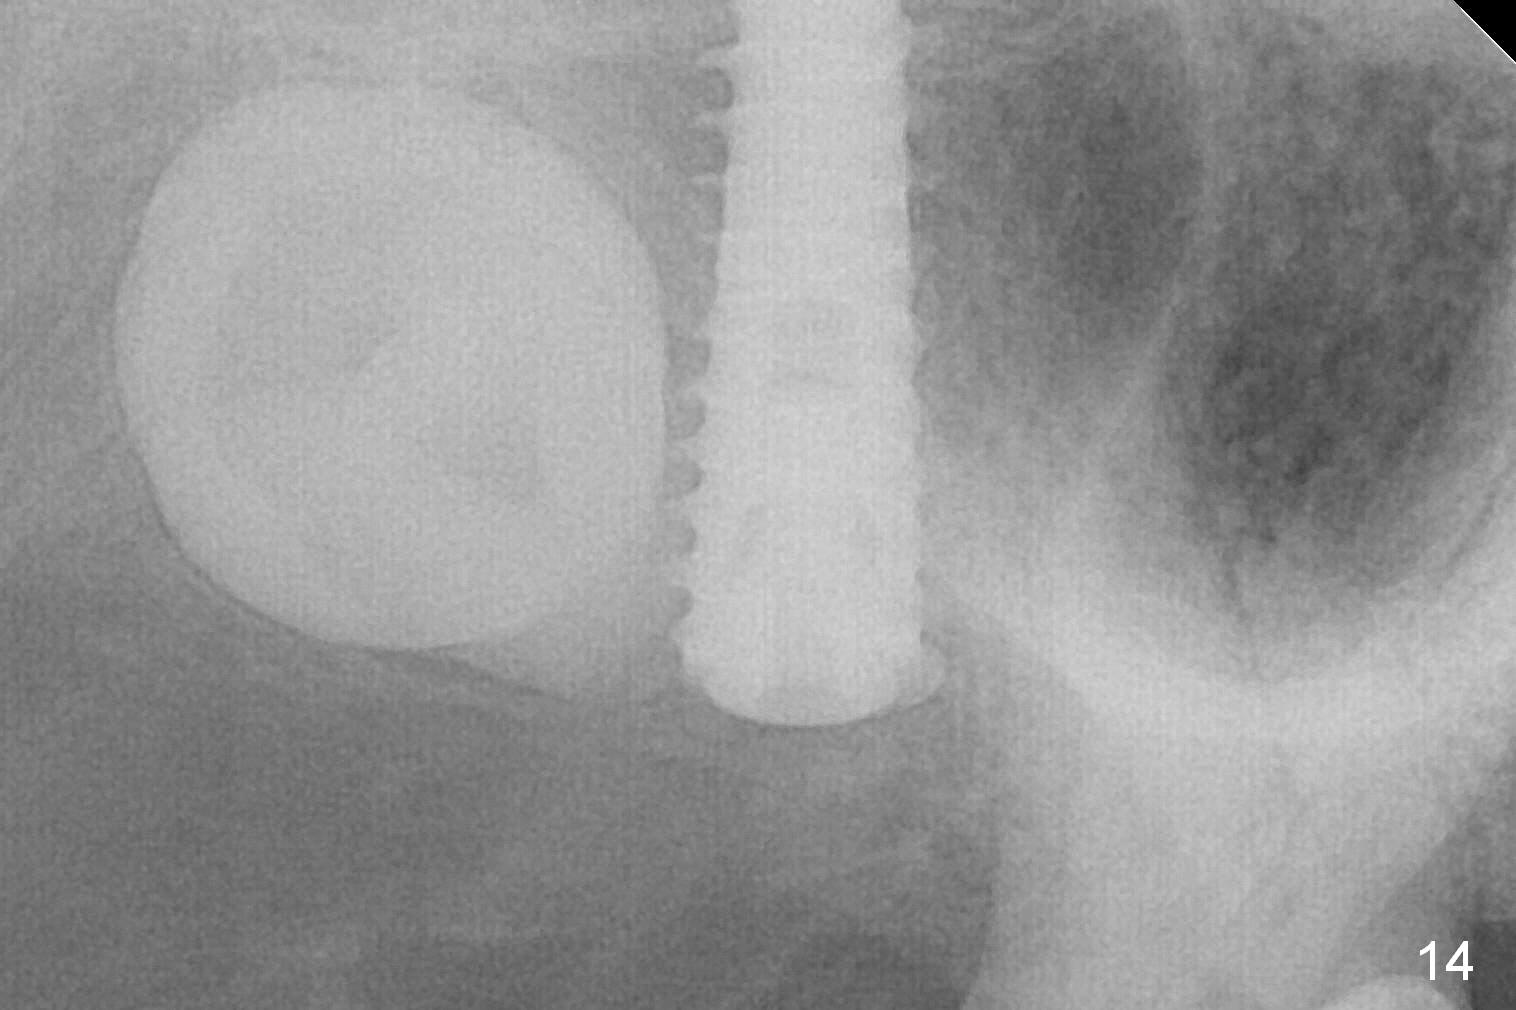

Extraction confirms crack tooth at #2 (Fig.1 (mesial view) <). The buccal (Fig.2 (illustration) B) socket is larger than the palatal (P) one, while the septum (S) is small. Osteotomy is initiated on the buccal slope of the septum (Fig.3 red arrow), followed by Magic osteotomes (Fig.4-7). As the diameter of the osteotomes increases, so does the depth with sinus lift (Fig.5 arrow). The largest osteotome is 4.8 mm. When a 5x13 mm implant is placed, it has low torque (Fig.8,9). The implant resists lateral movement, but keeps turning. When a largest pair abutment with the longest cuff is placed (6.5x4(4) mm to hold an immediate provisional in place), it seems to turn with the underlying implant together for a half turn. Since the provisional is engaged into the distal undercut of the tooth #3 (while the acrylic is setting), it may increase the implant stability. Anyway, overprep in this case leads to low primary stability. For immediate implant, underprep is a must. For this case, the last osteotome should have been 4.3 mm (.7 mm (one or two size(s)) smaller than the implant). When the implant is found to have low torque value, remove it, place bone graft in the osteotomy site and surrounding socket for sinus lift as well and place the implant again. The primary stability should have been increased. Preferably, a larger implant should be used (5.5 mm). Fortunately there is nasal hemorrhage postop. Reexamination of the extracted tooth after being soaked in bleach for 2 days confirms that the mesial (Fig.10 M) and distal (Fig.11 D,12 <) crack lines extend intrapulpally (^).

In fact, the implant is reversely torqued (1 month postop) and ~ 2 mm more coronally. It becomes looser. A healing screw is placed. With insertion of collagen plug, sutures are placed. Five days postop, the wound appears to be healing with sutures being dissolved. Four months later (5 months post placement), the patient returns asymptomatic. The wound heals. The implant appears to have osteointegrated and is at the crestal level (Fig.13,14). At uncover, the implant is found unstable; a healing abutment is placed. The implant is stable 8 months postop with apparently no gap between the bone and threads (Fig.15, as compared to Fig.13).